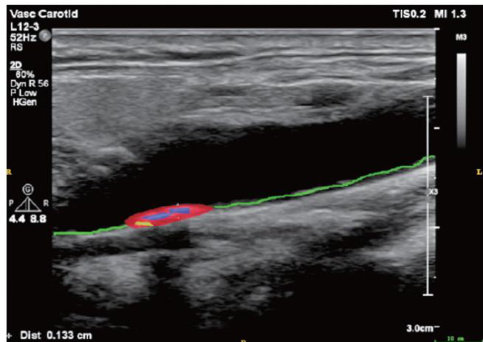

ABSTRACTCarotidatherosclerotic plaques(CAP)have become a significant risk factor forcardiovascular and cerebrovasculardiseases,suchasischemicstroke.Earlyidentificationofplaqueriskiscrucialforstrokeprevention.Ulrasound playsan importantroleinthediagnosisofCPA,itnotonlyassesss plaquesizeand morphologybutalsoprovides hmodyamic characteristics,therebyevaluating plaque stabilityandvulnerability.However,theaccuracyoftraditional examinationmethods is oftenlimitedbyfactors,suchasoperator experienceandequipmentresolution.The introductionofAItechnology,particularly deeplearning algorithms,hasbecomeanimportantaproach toenhancing clinical diagnosticprecisionandeficiency.This articlefocusesontheaplicationofAIintheultrasounddiagnosisofCAPinrecentyears,discusses itsapplicationinautomatic plaqueimagesgmetation,lassifcatio,issuecomponentientifiation,andstabilityassessment,andprovdesandepth analysis of the advantages,disadvantages,and challenges faced by current inteligent ultrasound diagnosis of CAP.